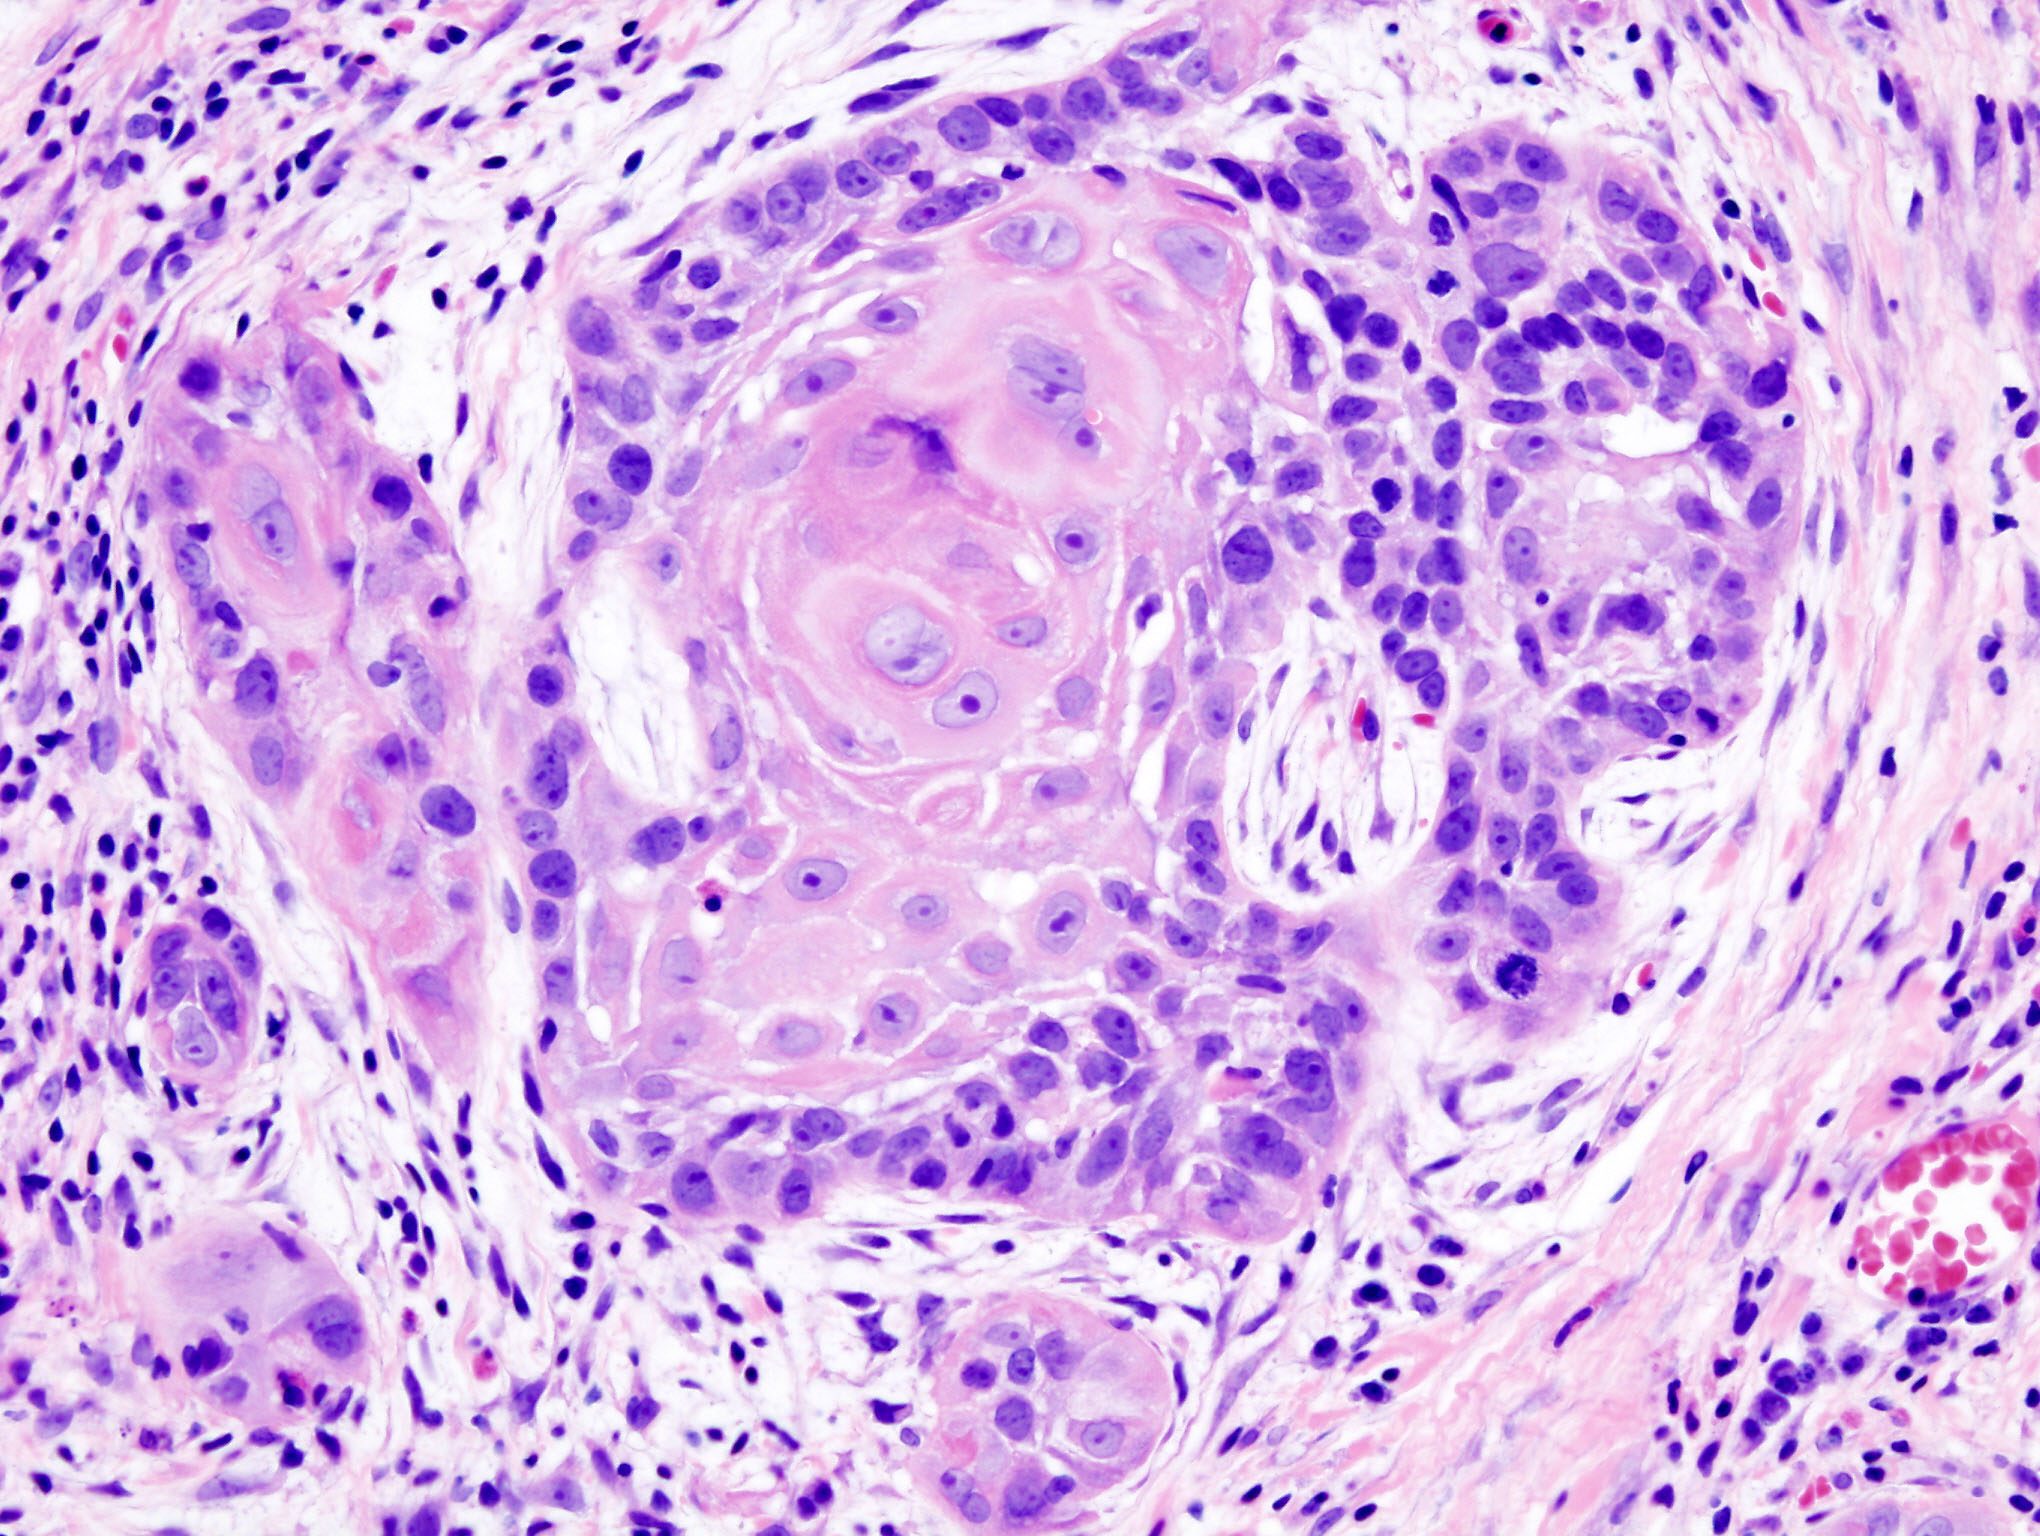

Berücksichtigung der Tumormikroumgebung eröffnet neue Therapieoptionen